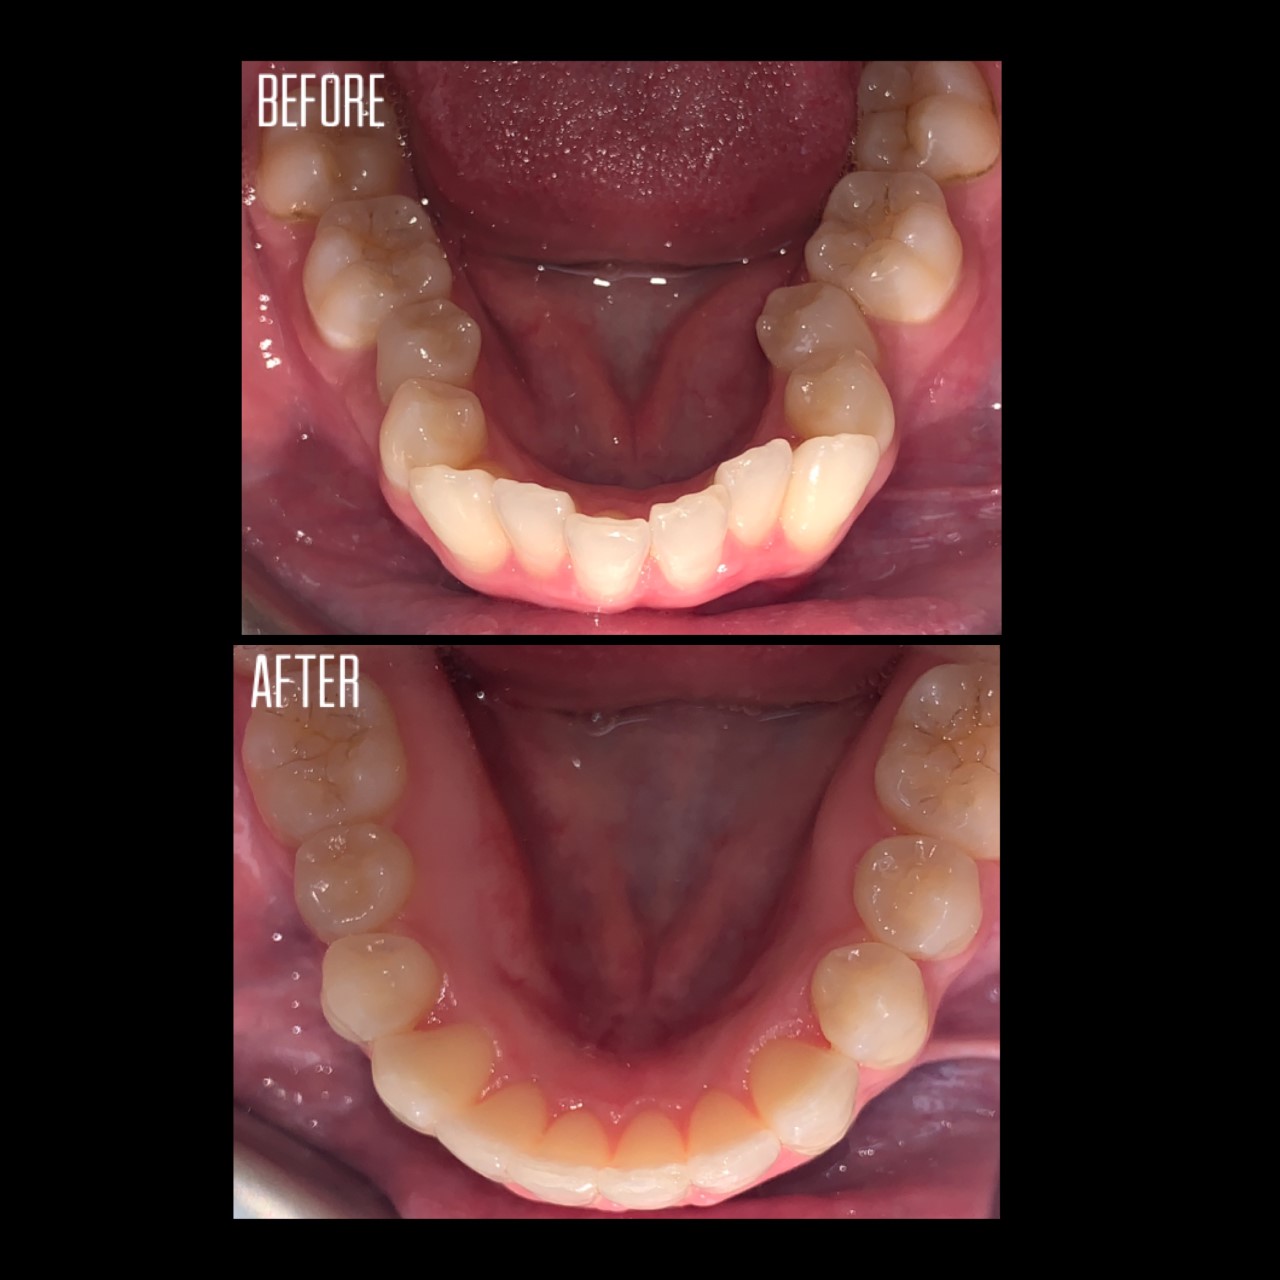

Gallery